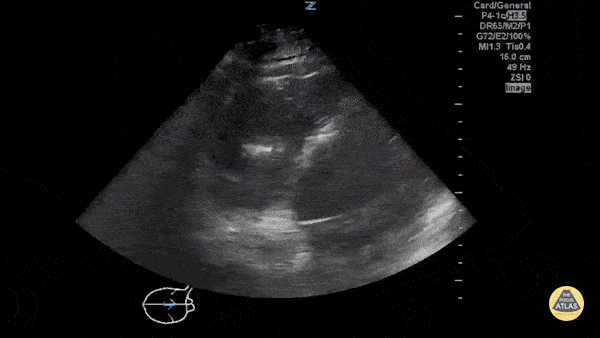

Disorganized cardiac activity consistent with ventricular fibrillation. Sukh Singh, MD